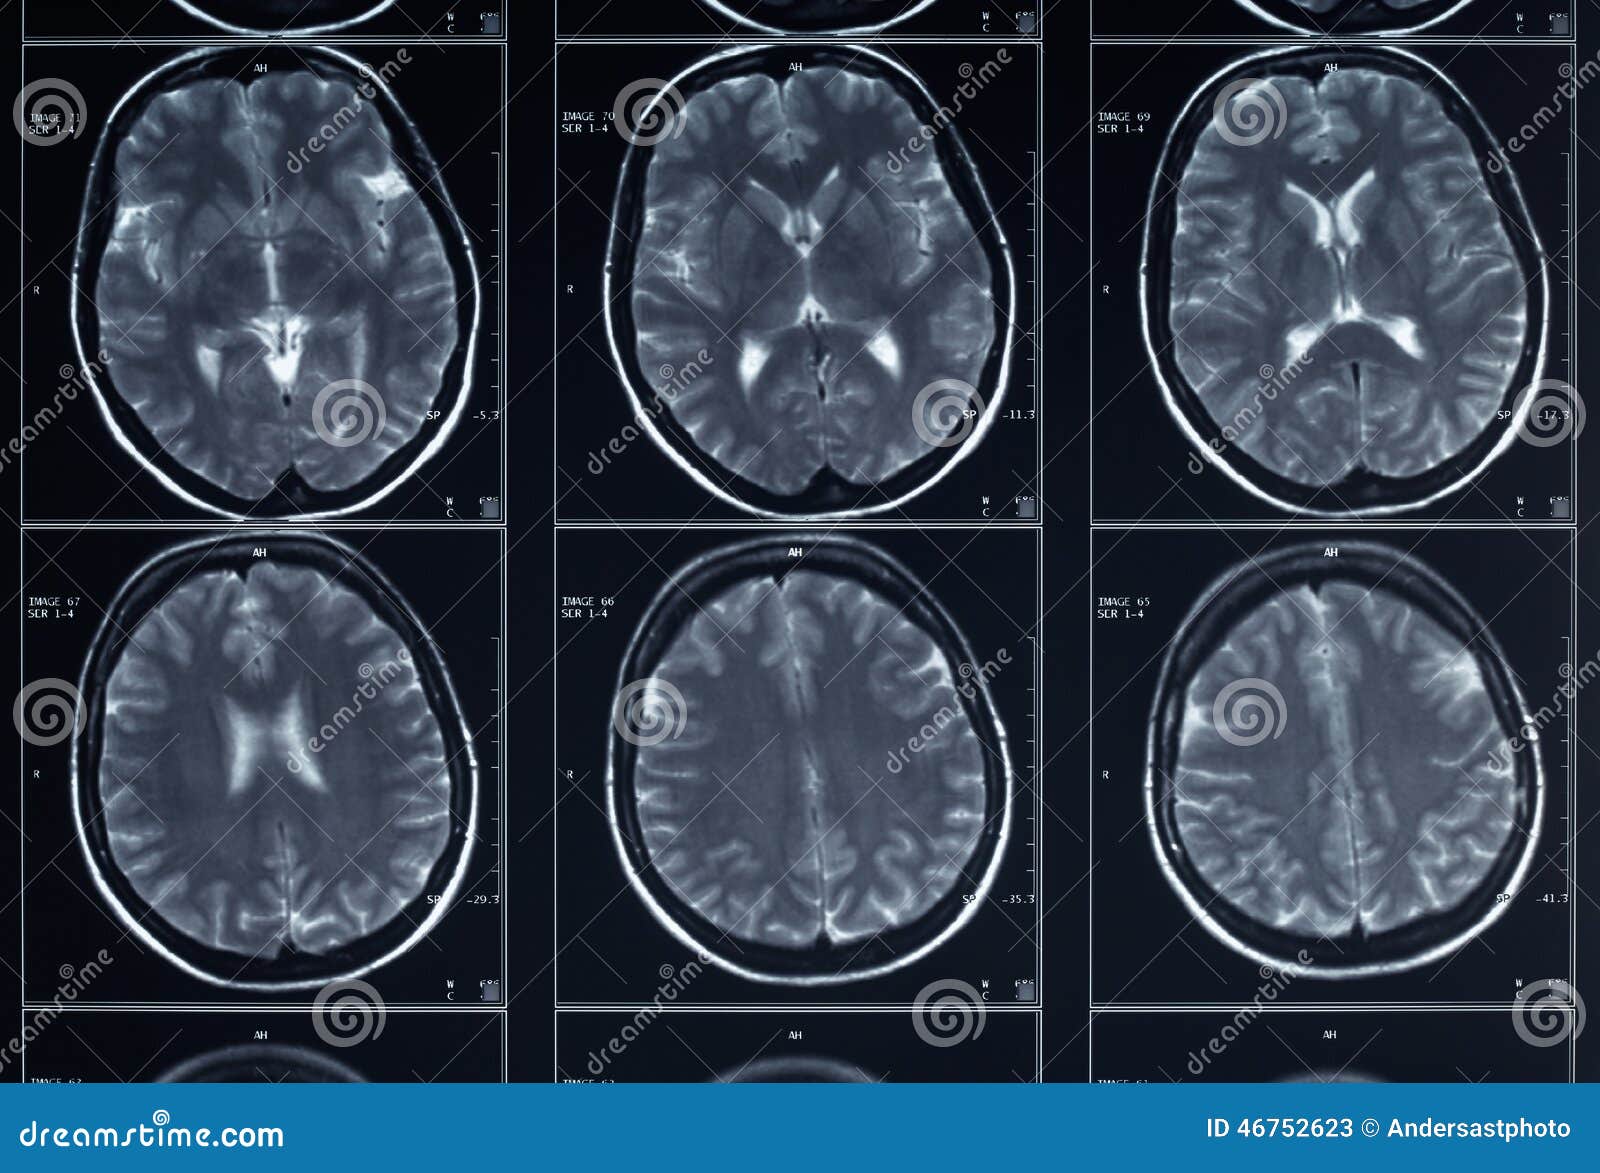

L Imaging Dell Encefalo Tc Ed Rm A Confronto

Risonanza Magnetica Encefalo Medical Imaging Caserta

Tecniche Di Diagnostica Per Immagini In Neurologia

Risonanza Magnetica Encefalo A Cosa Serve Radiologia Italia

Atlante Di Resonanza Magnetica Del Cervello